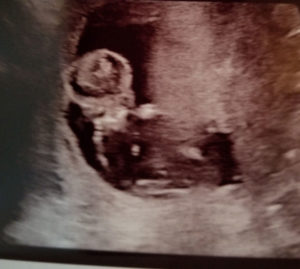

Reversal Surgery Worked! Our Cupcake Is Doing Great!

Little Baby Is Doing Great!

our-reversal-baby-is-our-little-cupcakeSeriously my heart is full of so much love. Our little cupcake or stud muffin…is doing great.

The heart rate at 153 and was bouncing all over the place.

Dr. Montieth is seriously amazing!